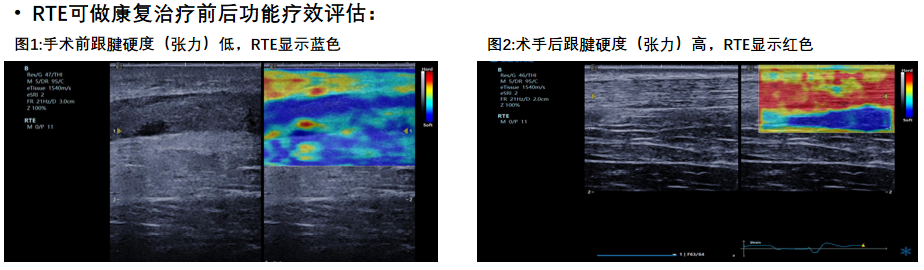

RTE实时弹性成像

?肌骨系统组织的硬度可反应炎症的严重程度?肌肉肌腱组织进行弹性测定,有助于检测创伤性及退变性病变?肌肉肌腱炎性程度评估?精准定位肌痛点?治疗前后功能疗效评估